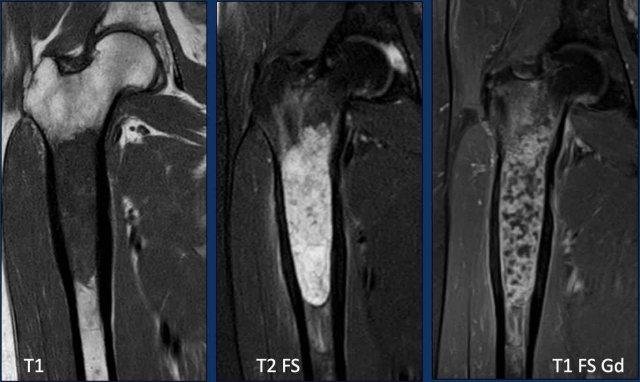

Hình ảnh

Hình ảnh T1W cho thấy sự thay thế tủy xương.

Hình ảnh T2W cho thấy phản ứng màng xương

và phù tủy xương quanh tổn thương.

Bản thân khối u tăng tín hiệu và

có dạng nốt.

Hình ảnh T1W FS sau tiêm Gd cho thấy

hình thái ngấm thuốc dạng vòng và cung.

Kết luận

Tất cả những phát hiện này phù hợp với một khối u sụn, và rất nghi ngờ là u sụn ác tính độ II hoặc cao hơn.

Tại trung tâm chuyên khoa tuyến ba về sarcoma xương của chúng tôi, chúng tôi không thực hiện sinh thiết đối với các khối u sụn này, vì điều này có thể gây ra sai số lấy mẫu do tính không đồng nhất bên trong khối u.

Bạn có thể vô tình sinh thiết vào phần lành tính hơn của khối u và đánh giá thấp độ mô học.

Các khối u sụn được biết đến với khả năng gieo rắc theo đường sinh thiết.

Điều trị bao gồm cắt bỏ khối xương đùi gần và tái tạo bằng nội khớp giả.

Pathology confirmed a chondrosarcoma grade II.

Chondrosarcoma độ II và độ III không thể phân biệt dựa trên hình ảnh học.

Đây là chẩn đoán được thực hiện dựa trên mô bệnh học.

Do đó, chúng tôi gọi các tổn thương như vậy là “độ II hoặc cao hơn” trong báo cáo chẩn đoán hình ảnh của chúng tôi.